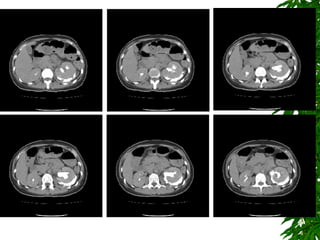

CT scan of abdomen (Day 6) 1. Tear of posterio-inferior wall of extra-renal portion of L't renal pelvis, with extravasating contrast media in L't peri-renal space. 2. L't hydronephrosis and L‘t hydroureter. 3. Post-partum enlarged uterus noted. Arrange L't Percutaneus nephrostomy (PCN) under the fluoroscopic guidance (after IVP study)

CT scan ofabdomen (Day 6) 1. Tear of posterio-inferior wall of extra-renal portion of L't renal pelvis, with extravasating contrast media in L't peri-renal space. 2. L't hydronephrosis and L‘t hydroureter. 3. Post-partum enlarged uterus noted. Arrange L't Percutaneus nephrostomy (PCN) under the fluoroscopic guidance (after IVP study)